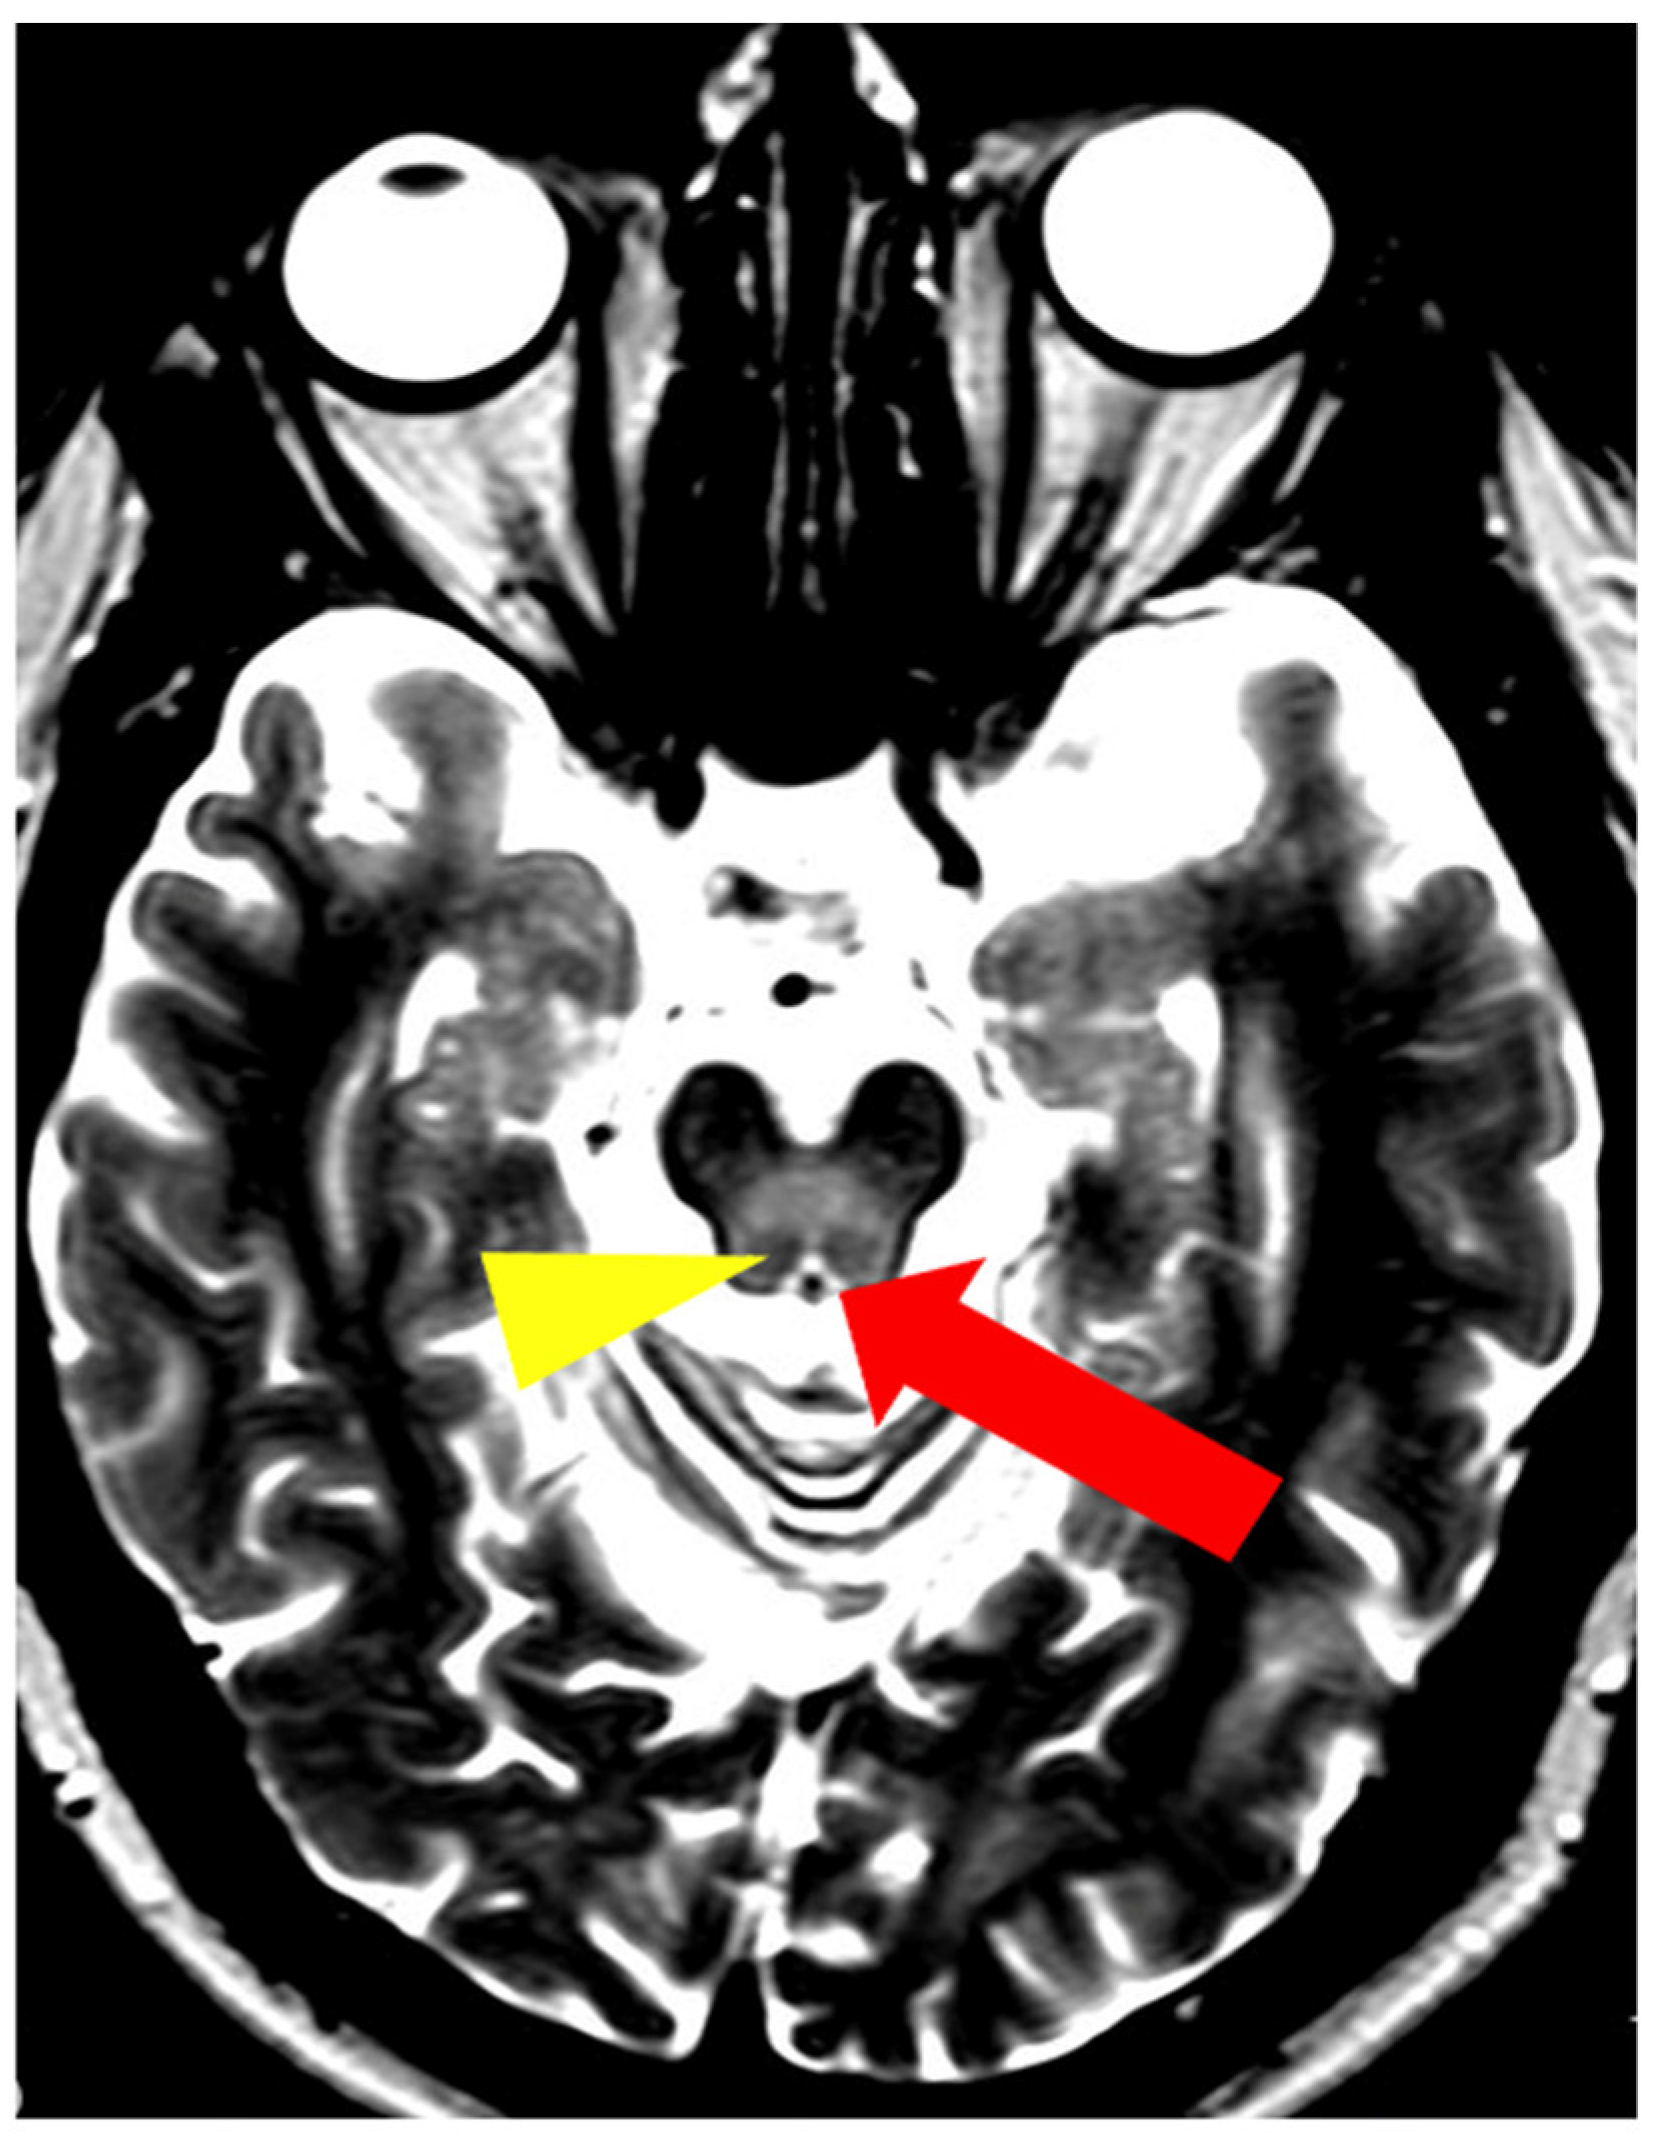

5. Neuroradiological Pathognomonic Signs of WD

- Rędzia-Ogrodnik, B.; Członkowska, A.; Antos, A.; Bembenek, J.; Kurkowska-Jastrzębska, I.; Przybyłkowski, A.; Skowrońska, M.; Smoliński, Ł.; Litwin, T. Pathognomonic neuroradiological signs in Wilson’s disease—Truth or myth? Park. Relat. Disord. 2023, 107, 105247. [Google Scholar] [CrossRef] [PubMed]

- Hitoshi, S.; Iwata, M.; Yoshikawa, K. Mid-brain pathology of Wilson’s disease: MRI analysis of three cases. J. Neurol. Neurosurg. Psychiatry 1991, 54, 624–626. [Google Scholar] [CrossRef] [PubMed]

- George, U.; Varte, N.; Rathore, S.; Jain, V.; Goyal, S. “Split thalamus”: Internal medullary involvement in Wilson’s disease. Neurol. India 2010, 58, 680. [Google Scholar] [CrossRef] [PubMed]

- Sener, R.N. The claustrum on MRI: Normal anatomy, and the bright claustrum as a new sign in Wilson’s disease. Pediatr. Radiol. 1993, 23, 594–596. [Google Scholar] [CrossRef] [PubMed]